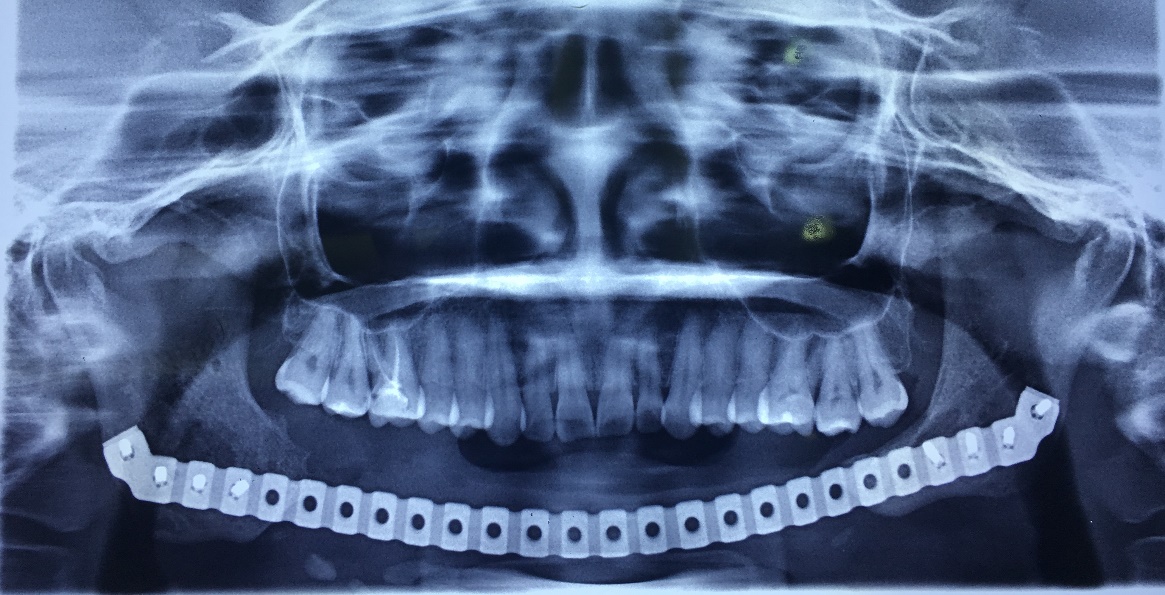

X-Quang sau cấy ghép răng (Implant)